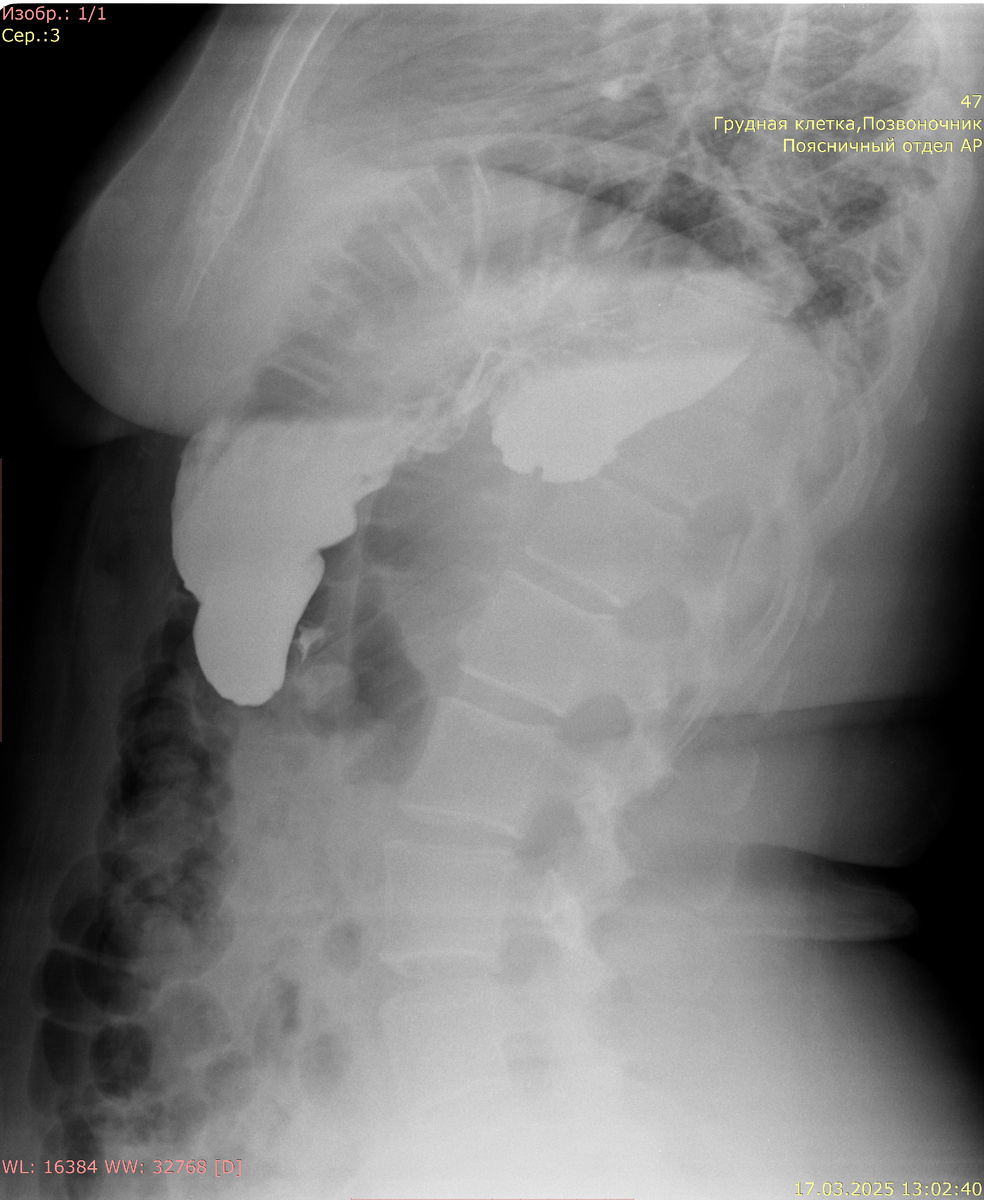

Рентгенография желудка с сульфатом Ва:

Кардиальный жом функционирует. Желудок не деформирован, объем обычный, смещаемость не нарушена. Контуры желудка ровные, отвесные, участков деформации не выявлено. Рельеф слизистой не изменен, складки не утолщены. Контраст своевременно поступает в ДПК. В положении лежа при натуживании определяется пролабирование кардиальных складок выше диафрагмы размерами 66 мм х 61 мм.

Заключение: Скользящая грыжа пищеводного отверстия диафрагмы 3-4 ст.